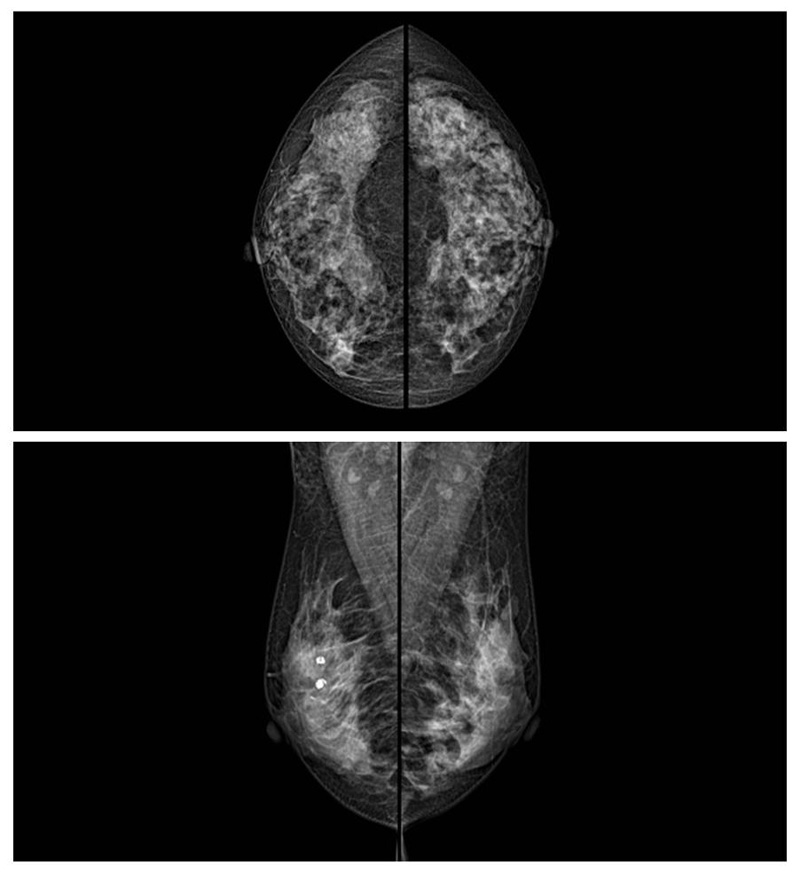

乳腺癌的發(fā)生率越來越高,已經(jīng)是我們國家的癌癥之一已成為女性健康“頭號(hào)殺手”。乳腺DR可提高乳腺癌早期檢出率并精準(zhǔn)定位。發(fā)現(xiàn)和診斷早期乳腺癌最有效的方法之一,明顯利大于弊女性都要重視乳腺的檢查。輻射很小最簡便、最可靠、無創(chuàng)性檢查手段,做一次乳腺DR的劑量相當(dāng)于7周的正常生活。尤其是對(duì)于40歲以上的女性尤為重要,那么乳腺DR是怎么進(jìn)行檢查的呢?我們來了解一下,為廣大朋友在檢查前有點(diǎn)心理準(zhǔn)備。檢查時(shí)候是避開經(jīng)期的前后,月經(jīng)來后的7天左右比較合適。需要脫衣服檢查,根據(jù)拍片的擺位要求,有頭尾位置,內(nèi)外斜位,還有側(cè)位。定點(diǎn)放大壓迫方法可以更細(xì)微清晰的檢查出病灶。